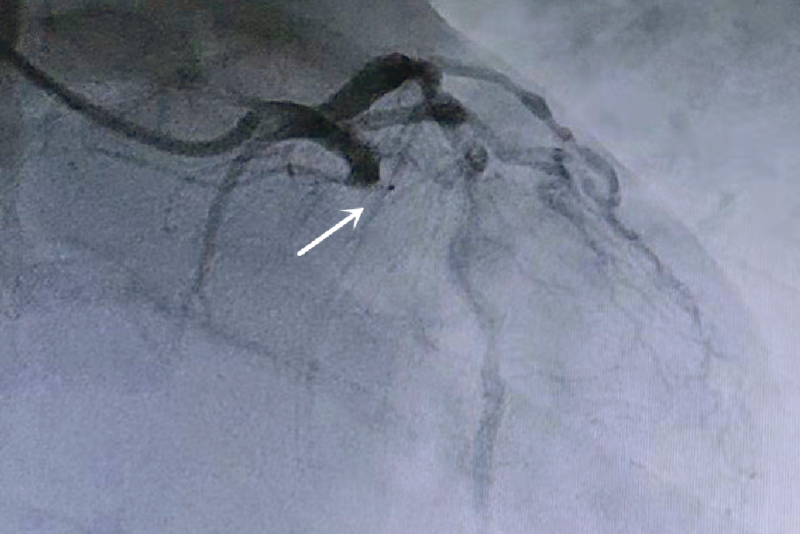

造影显示患者的冠状动脉回旋支近段完全闭塞。(翻拍照片)

时间就是心肌,时间就是生命。待向患者交代病情,并征得其同意后,北院心内一科李强主任与陈金贺、孙青两位医生紧急为患者做了经皮冠状动脉介入治疗术,患者转危为安,及时避免了重大风险,并于近日出院。